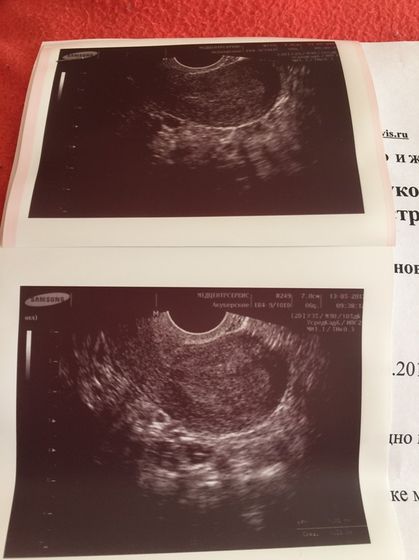

Сходила на УЗИ ели ели видно, ну есть все же сказала 90% беременность во вторник ещё раз на УЗИ к ней идти нужно… завтра в обед хгч будет готов

Отличное УЗИ… здоровья вам ?? и сил!!! Очень хорошее УЗИ и врач, если увидели так рано, такое маленькое, все будет хорошо ??